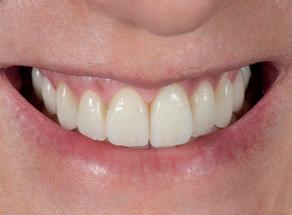

De assinalar que o desgaste do esmalte vestibular, proximal e incisal dos dentes preparados foi quase nulo e a preservação da vitalidade pulpar foi conseguida em todos os dentes (Fig. 3).

Decidiu-se descruzar a mordida e preencher os corredores vestibulares à custa de aderir umas facetas com um volume vestibular e um aumento do comprimento dos dentes bastante considerável (Fig. 4).

Figura 4

MARÇO 2011 MARÇO 2017